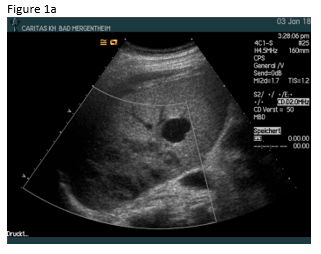

A 49 year old patient was admitted to the hospital for sepsis and shock of unknown origin. The patient presented with signs of sepsis and hemodynamic instability that justified an urgent approach including complex intensive care and intubation. Bedside ultrasound (US) found ascites and an abscess in the right liver lobe (9 cm) (Figure 1a). The patient was treated with broad-spectrum antibiotics and puncture and drainage of the abscess (Figures 1 a-c and 2 a-b). In addition, a biopsy was taken from the periphery of the lesion. A few days after the removal of the drainage the patient presented with a progressive elevation of liver enzymes. US revealed a cystic lesion measuring 30 mm that was proximal to the drained abscess (Figure 1a). Color Doppler Imaging (CDI) showed arterial flow inside the lesion, and contrast enhanced ultrasound (CEUS) showed early arterial enhancement and turbulent flow with a “to-and-fro” sign, suggestive of a pseudoaneurysm (Figure 1b). There was also a heterogeneously vascularized lesion with enhancing septae in the surrounding liver parenchyma (Figure 1c) . A few days later the patient presented with tachycardia and a drop of hemoglobin from 10 g/dl to 7 g/dl. US revealed spontaneous thrombosis of the pseudoaneurysm (Figure 1d) with intra - and perihepatic hemorrhage (Figure 1e).

Phlegmonous inflammation and abscess formations show variable and sometimes confusing US B-mode findings, which may change over time. The surrounding hypervascularitiy of abscesses may support the development of pseudoaneurysm after puncture and drainage in a few patients. On B-mode US pseudoaneurysms may appear like a cystic tumor, therefore CDI should be preferred as the primary screening technique for detection of vascular complications. The swirling colour pattern of the flow within the pseudoaneurysm that mimicks the "yin-yang" symbol (so called “to-and-fro” pattern) and the presence of high velocity are characteristic features of these lesions [(1-3)].